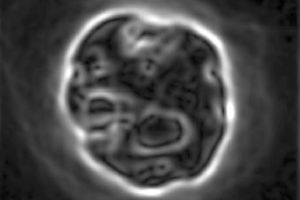

The result is a large data set of "pseudo-projections," generated as the sample tube rotates. Algorithms adapted from those used in an analogous fashion for conventional CT images then turn the slices of visual data into a 3D image of the stained nuclear material of the specimen, with a resolution of 0.35 microns.

Crucially, the technique could help to spot aneuploidy in small numbers of sample cells, potentially revealing the presence of cancer before other clinical signs materialize. Flow cytometry works on large numbers of cells and assesses whole populations, making it less able to spot the rare abnormality in a limited group of cells; but OPTM could be ideal.